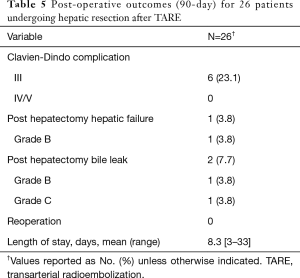

There were no grade III or higher bilirubin toxicities after TARE prior to hepatic resection. One patient developed grade III diarrhea and another developed grade III abdominal pain after TARE. Post operative outcomes are given in Table 5. The majority of patients had no major complications (n=20, 76.9%) and had hospitalizations less than 9 days (n=23, 88.5%). The incidence of PHLF was 3.8% (n=1). There were no reoperations or mortalities within 90 days.

Full table